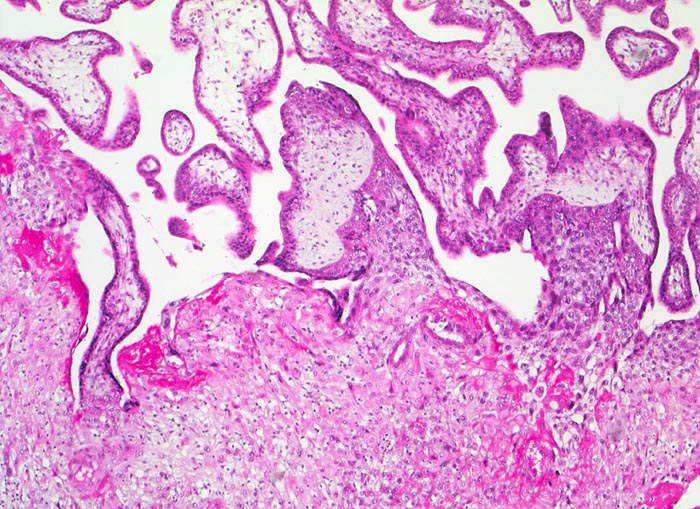

Morphologische Merkmale:

• Myometrium bedeckt von dezidualisiertem Endometriumstroma der Dezidua basalis.

• Invasion des Myometriums durch intermediären extravillösen Trophoblast.

• Fibrinoidschicht.

• Chorionzotten, ein Teil davon verankert mit dem dezidual transformierten Endometrium = Dezidua basalis (Haftzotten).

• Choriondeckplatte.

• Rechts oben Anteile des Chorion laeve.